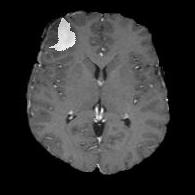

We argue that the sub-optimal paradigm of processing different abstractions within a single CNN pipeline can be remedied through the effective processing of information in a structured manner. Consequently, we devise strategies for disentangling the edge and texture information within a single training pipeline. Figure 2 illustrates how our proposed module, dubbed EG-CNN, can be paired with any existing CNN encoder-decoder to improve segmentation quality near intensity edges. We have applied our EG-CNN to the tasks of brain and liver tumor segmentation in medical images (Figure 3).

(1) Brain MR (2) Liver MR (3) Liver CT (4) Lung CT